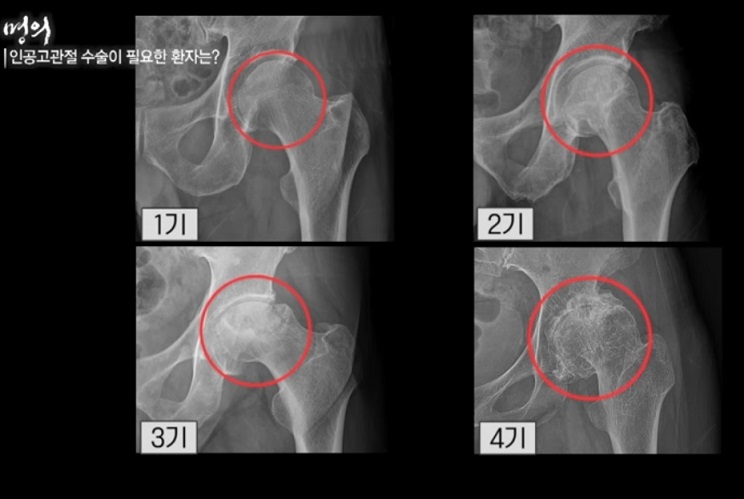

- 인공 고관절 수술이 필요한 환자는?

그렇다면 젊은 환자들은 언제 인공 고관절 수술을 받아야 할까?

또 고령 환자가 늘고 있는 상황에서 몇 살까지 수술이 가능할까? 인공고관절 수술의 적기와 수술 후 관리법에 대해 명의에서 공개한다.